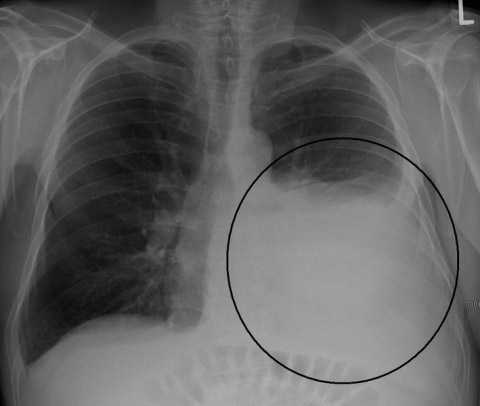

Π ΠΈΡ. 4. Π‘ΠΊΠΎΠΏΠ»Π΅Π½ΠΈΠ΅ ΠΆΠΈΠ΄ΠΊΠΎΡΡΠΈ Π² Π»Π΅Π²ΠΎΠΉ ΠΏΠ»Π΅Π²ΡΠ°Π»ΡΠ½ΠΎΠΉ ΠΏΠΎΠ»ΠΎΡΡΠΈ β ΠΎΡΠ½ΠΎΠ²Π½ΠΎΠΉ ΠΏΡΠΈΠ·Π½Π°ΠΊ ΡΡΠ±Π΅ΡΠΊΡΠ»Π΅Π·Π½ΠΎΠ³ΠΎ ΠΏΠ»Π΅Π²ΡΠΈΡΠ°.